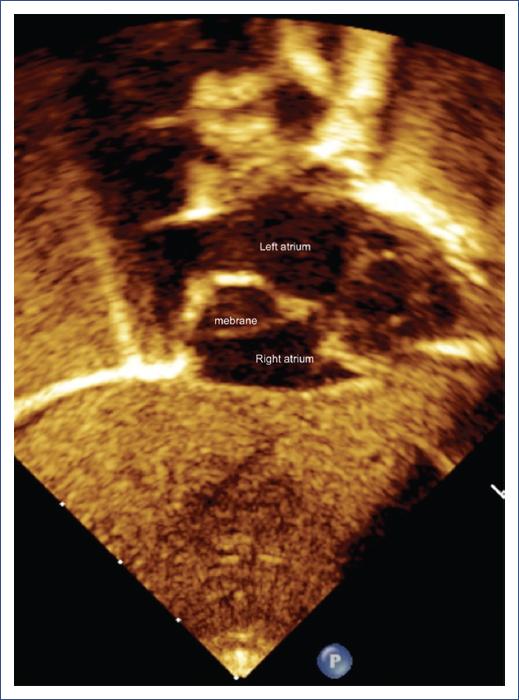

An echocardiogram showed normal drainage of pulmonary veins, with a membrane in the roof separating the RA into two cavities, the small upper cavity connecting to the left atrium through the patent foramen ovale (Fig. 1). This explained the right-to-left shunt and cyanosis. A diagnosis of ASD and complete CTD was made.

Figure 1 Echocardiography, subcostal view. The arrow shows the membrane (Cor triatriatum dexter) inside the right atrium.